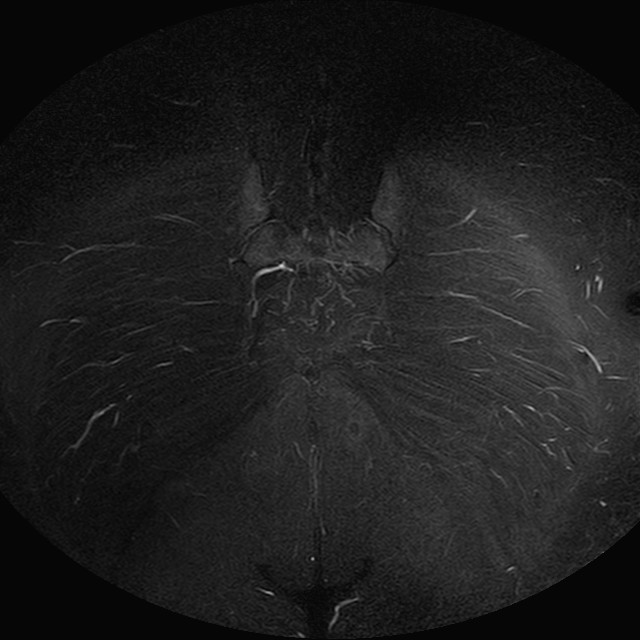

Esami: RMN BACINO

eSTIR

Evidenti e simmetriche alterazioni osteofitosiche in regione coxo femorale con riduzione delle rime articolari. Degenerazione completa del cercine glenoideo. Non attuali segni di versamento articolare. Non segni di edema osseo che escludono attuale algodistrofia od osteonecrosi. Lieve e simmetrica riduzione del trofismo della muscolatura glutea.